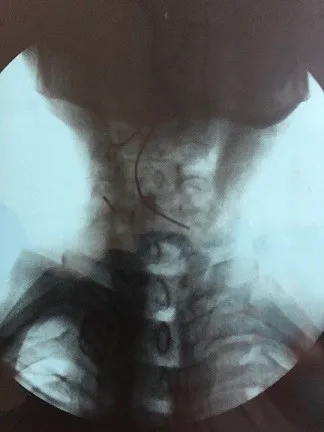

耳鼻喉科門診主任張峰接診后立即給予常規(guī)檢查,老人患小腦萎縮多年,拒絕張嘴,不配合檢查,給予頸部平片檢查發(fā)現(xiàn)喉部巨大異物,異物內(nèi)見金屬絲,根據(jù)陰影形態(tài)能夠確定喉部異物系全口義齒。